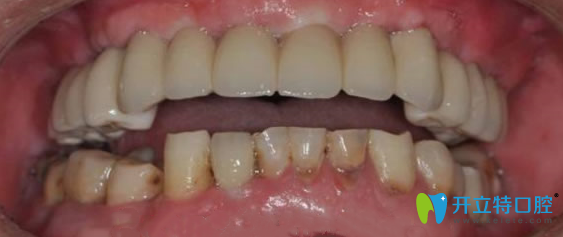

張叔戴上牙冠后:

經(jīng)過6個(gè)月的恢復(fù)期后,田醫(yī)生檢查確認(rèn),牙槽骨和種植體緊密結(jié)合,為他裝上了牙冠。完成種植牙全過程,張叔真是人老心不老呀!裝上牙冠后,急著照鏡子看看南京金臺口腔牙齒種植后的效果怎么樣?看著一排整齊的牙齒,激動的說,原來我還可以這么帥,晚上一定要去飯店吃羊肉火鍋,過把癮。

金臺口腔半口牙缺失術(shù)后效果圖: